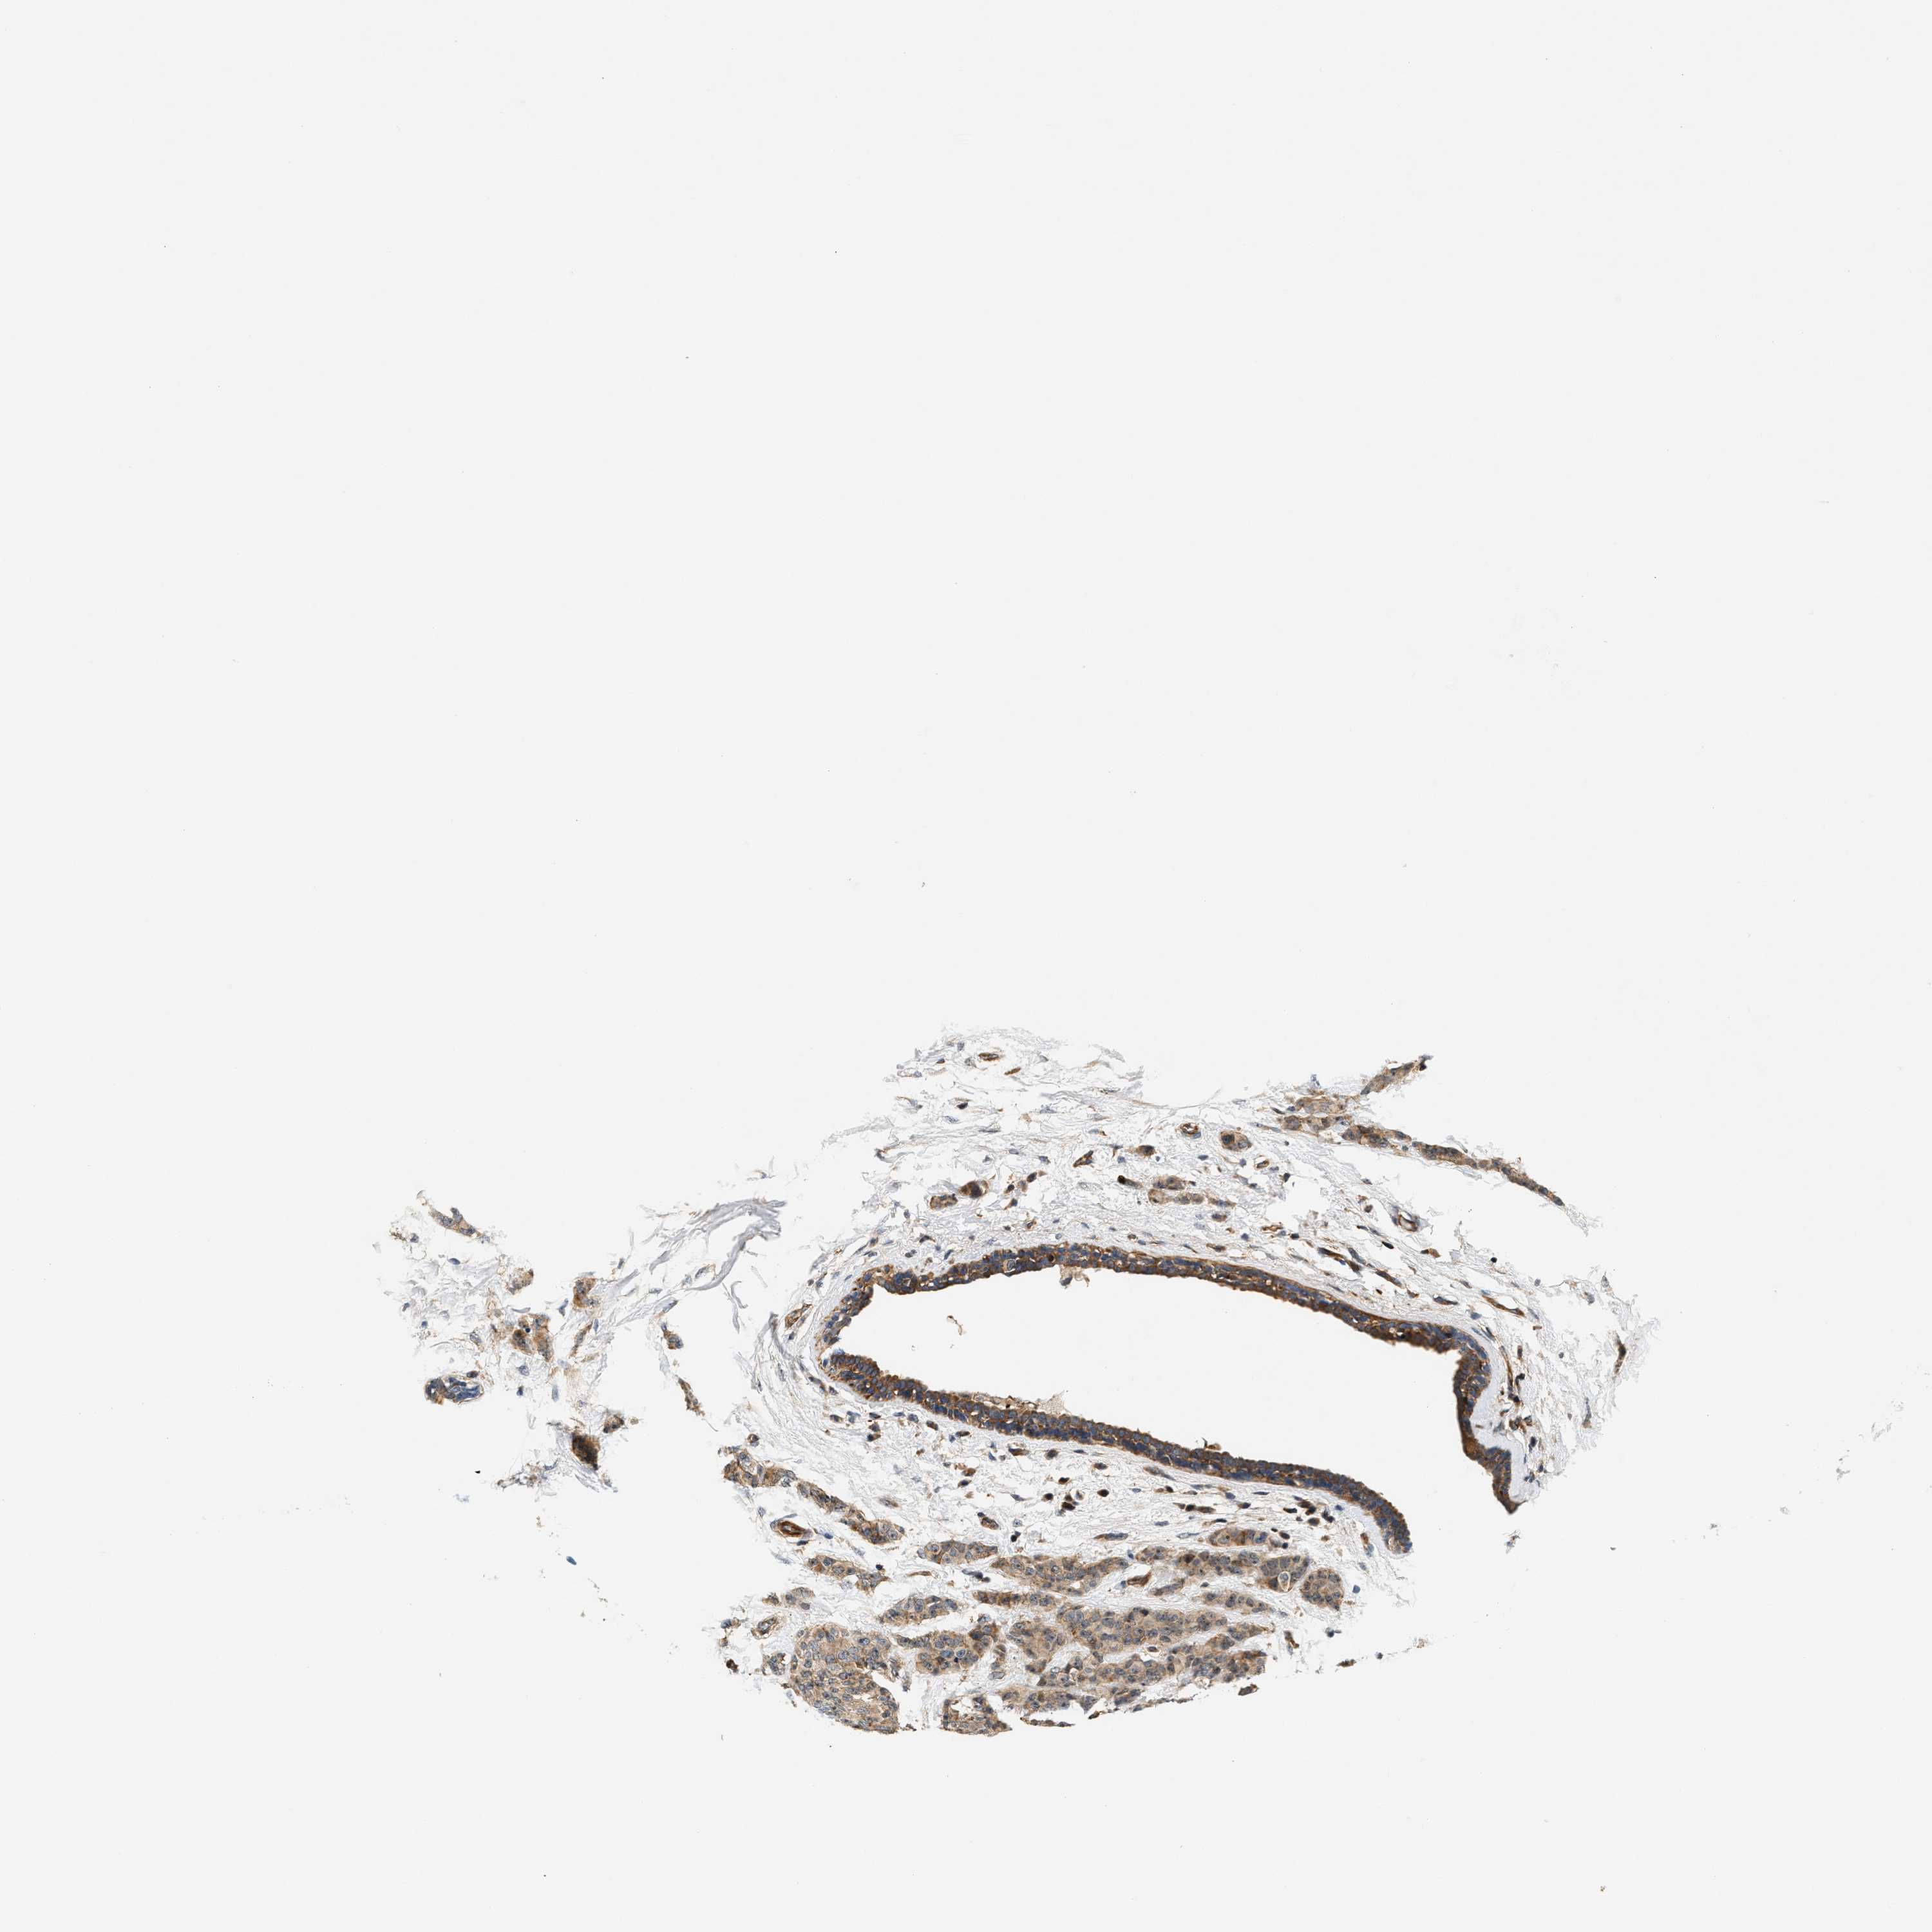

CANCER BREAST CANCER Show tissue menu

BRCA TCGA BRCA VALIDATION PROTEIN EXPRESSION

Breast cancer

Human cancer